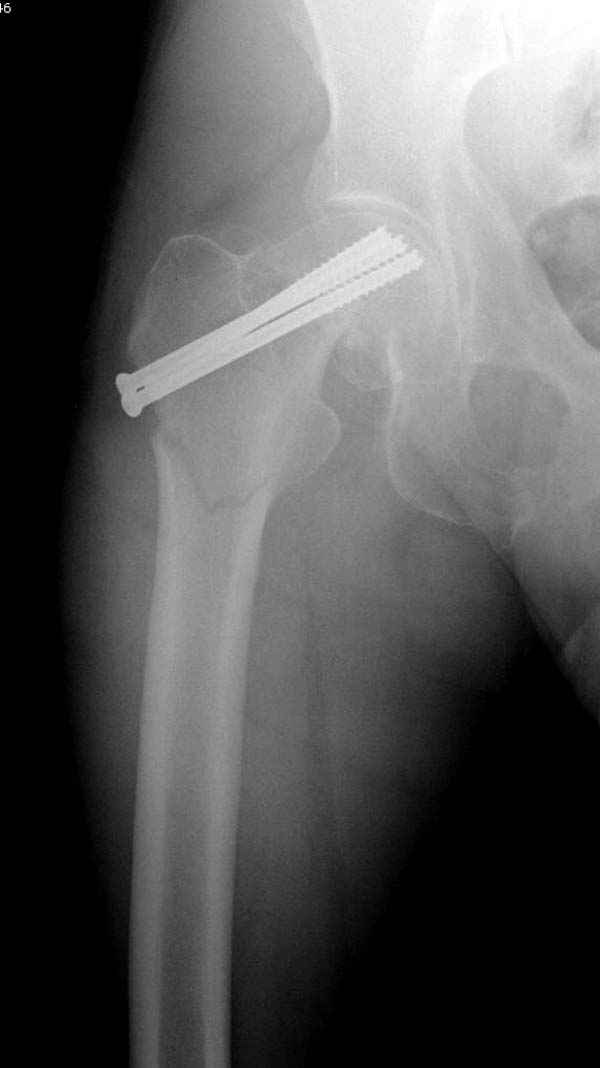

Профилактику дальнейшего раскола неполного перелома шейки провели тремя канюлированными шурупами.

На второй день после выписки упал дома. Снимки приложены. Коллеги рекомендуют удаление шурупа и вытяжение. Что делать?